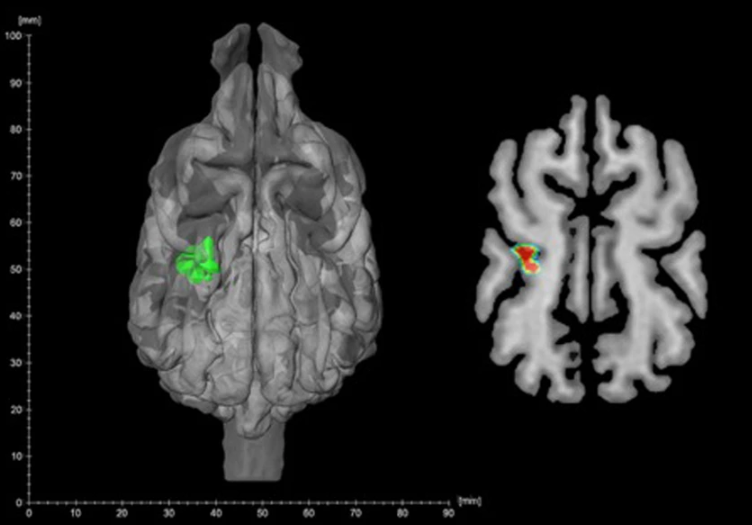

同时,罗兰大学的科学家使用磁共振成像技术观察了狗狗大脑不同区域对热刺激的反应情况,这些温度与其他实验大致相同。温度较高的物体会在左体感关联皮层(大脑处理感觉信息的部分)中引起反应,科学家得出结论认为,这很可能来自鼻腔(鼻子周围潮湿、无毛的皮肤)。